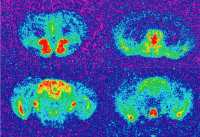

The brain’s mu opioid receptors, the same receptors targeted by morphine, are responsible for the depression-relieving effects of an antidepressant called tianeptine, reports a new study from researchers at Columbia University Irving Medical Center.

The researchers found that tianeptine fails to produce an antidepressant effect in mice when the mu opioid receptor is blocked with antagonists or genetically removed. A metabolite of tianeptine, called MC5, is probably the drug’s active ingredient and could be used to develop a more effective version of the antidepressant. (Medication adherence is low with tianeptine, as patients must take three doses of tianeptine per day.)

The best known agonist of the mu opioid receptor is morphine, which is a very effective pain killer but also a drug of abuse. The researchers found that tianeptine also reduces pain but does not result in tolerance or withdrawal like morphine. Tianeptine may have potential as a painkiller, but it has yet to be studied in that capacity.